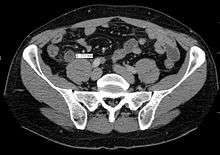

In children the clinical examination is important to determine which children with abdominal pain should receive immediate surgical consultation and which should receive diagnostic imaging.[40] Because of the health risks of exposing children to radiation, ultrasound is the preferred first choice with CT scan being a legitimate follow-up if the ultrasound is inconclusive.[41][42][43] CT scan is more accurate than ultrasound for the diagnosis of appendicitis in adults and adolescents. CT scan has a sensitivity of 94%, specificity of 95%. Ultrasonography had an overall sensitivity of 86%, a specificity of 81%.[44]

Computed tomography

Where it is readily available, computed tomography (CT) has become frequently used, especially in people whose diagnosis is not obvious on history and physical examination. Concerns about radiation tend to limit use of CT in pregnant women and children, especially with the increasingly widespread usage of MRI.[47][48]

The accurate diagnosis of appendicitis is multi-tiered, with the size of the appendix having the strongest positive predictive value, while indirect features can either increase or decrease sensitivity and specificity. A size of over 6 mm is both 95% sensitive and specific for appendicitis.[49]

However, because the appendix can be filled with fecal material, causing intraluminal distention, this criterion has shown limited utility in more recent meta analyses.[50] This is as opposed to ultrasound, in which the wall of the appendix can be more easily distinguished from intraluminal feces. In such scenarios, ancillary features such as increased wall enhancement as compared to adjacent bowel and inflammation of the surrounding fat, or fat stranding, can be supportive of the diagnosis, although their absence does not preclude it. In severe cases with perforation, an adjacent phlegmon or abscess can be seen. Dense fluid layering in the pelvis can also result, related to either pus or enteric spillage. When patients are thin or younger, the relative absence of fat can make the appendix and surrounding fat stranding difficult to see.[50]